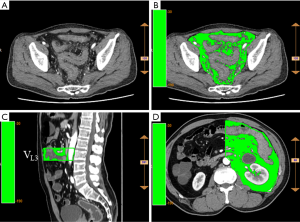

Measurement of left colonic and pelvic mesenteric adipose volume

The reconstructed images were analyzed according to the ANYTHINK GVCM system (CREALIFE Medical Technology, Beijing, China). The left colonic mesenteric adipose volume was measured in each vertebral space from the third lumbar vertebra to the first sacral vertebra (L3 to S1). The upper boundary of the pelvic mesenteric adipose volume was at the level of the S1 vertebra, and the lower boundary was at the hiatus of the levator ani muscle (Figure 1).

CT or MRI has been used to examine the area of adipose tissues on a single cross-section passing through the umbilicus in order to evaluate the total abdominal adipose content and the visceral adipose content (32-35). However, for rectal cancer patients receiving radiotherapy, this method has failed in measuring the ΔVp%. In this study, the reconstructed images were analyzed with the ANYTHINK GVCM system, through which we could continuously delineate the mesenteric area in any plane, and then calculate the total mesenteric adipose volume in the target area. This measurement has high reproducibility and provides a quantitative evaluation basis for comparing changes in abdominal and ΔVp%.